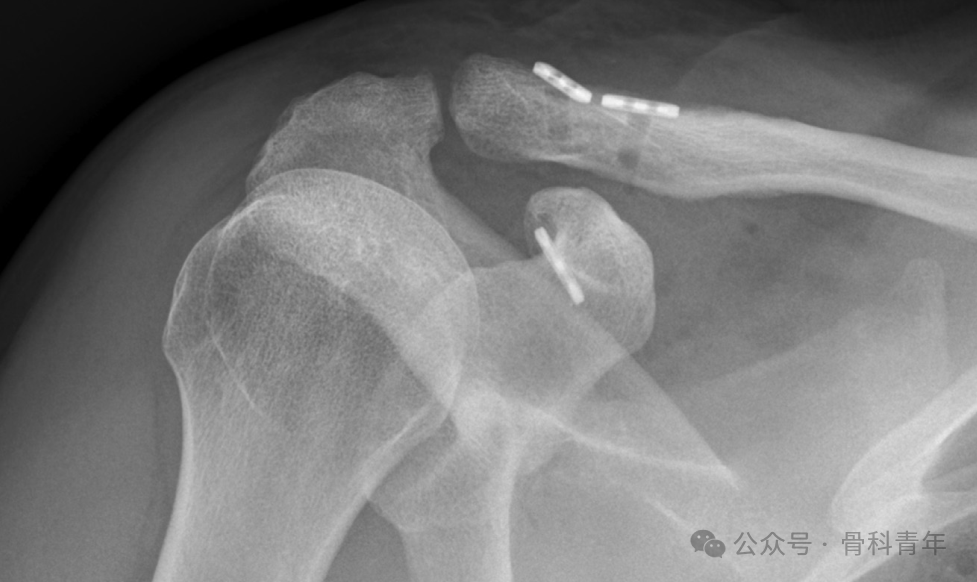

肩锁关节脱位是临床常见疾病,对Rockwood III-VI型肩锁关节脱位,为恢复肩锁关节稳定性及肩部正常活动,通常建议手术治疗。目前,肩锁关节脱位的手术内固定包括切开复位内固定(钩钢板、Tightrope)与关节镜下微创固定技术。

图片